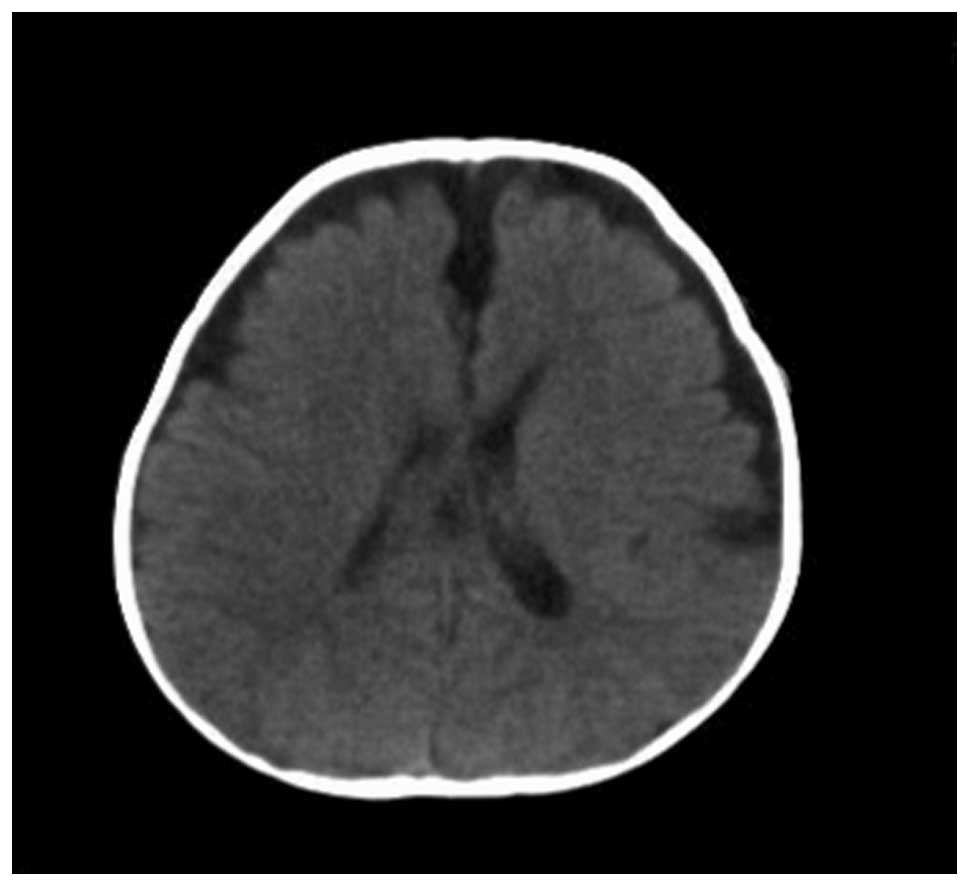

Application of 256-slice computed tomography with low radiation doses in neonates with hypoxic-ischemic encephalopathy

Hypoxic-ischemic encephalopathy (HIE), an injury or disease with lack of oxygen in the brain, may occur at any stage in childhood but the exact mechanisms that cause HIE remain unknown. In this study, 150 newborns suspected of having neonatal HIE and scheduled for a brain CT scan were randomly assigned to three equally sized groups as follows: standard dose group (120 kV, 250 mAsec), low dose group 1 (120 kV, 150 mAsec) and low dose group 2 (120 kV, 50 mAsec). All other acquisition parameters were the same in all groups. The CT dose index (CTDI), dose length product (DLP) and the image noise were compared among the three groups. The image quality was evaluated by blinded readers. The DLP of low dose group 2 was 19.3% of that of the standard dose group without a significant difference (P>0.05). The image noise of the low dose group 1 was greater than that of the standard dose group with a significant difference (P<0.01). Low dose scanning is feasible in the screening of HIE in neonates and is beneficial in protecting newborns against unnecessary radiation damage.